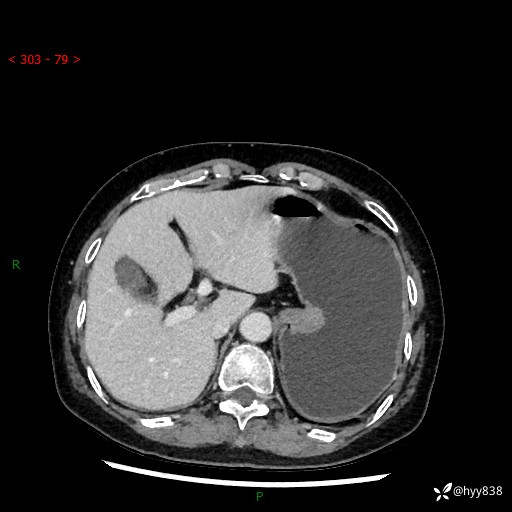

辅助检查:CT

胃CT平扫+增强(动脉期+静脉期)

三期CT值:46hu 58hu 75hu